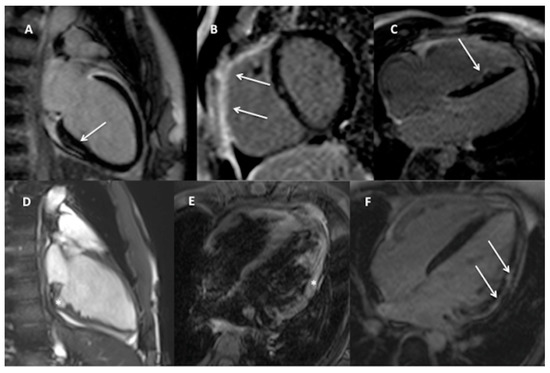

The examples of detected findings are shown on Figure 3.

Figure 3. Examples of potentially arrhythmogenic CMR findings in the studied cohort: (A). Two-chamber view, non-ischemic, subepicardial area of fibrosis in the basal infero-septal segment of the LV (arrow) without signs of myocardial oedema (not shown) in a 16-year-old girl with 12%/24 h of complex LBBB-like PVCs suggestive of previous myocarditis; Band (C)—regions of LGE (arrows) in the RV outflow tract and free wall ((B)—short-axis view) and in the interventricular septum (C)—4-chamber view) in a 17-year old boy with <1%/24 h complex LBBB-like PVCs and an overall small MRI criteria for ARVC. (D). Two-chamber cine view in end-diastole showing large crypt (asterisk) and irregular myocardial pattern of the inferior LV wall in a 13-year-old boy with 14%/24 h of RBBB-like PVCs, (E,F). 4-chamber view, signs of myocardial oedema (E—asterisk) and subepicardial, non-ischemic stria of fibrosis (F—arrows) in the lateral LV wall in a 14-year-old boy with <1%/24 h of complex undetermined PVCs indicative of acute myocarditis.